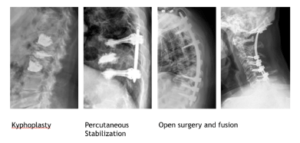

While radiation is effective it has no impact on spinal stability in the presence of pathological fractures. Mechanical instability presents usually with movement related pain at the level involved with possible radicular component. This pain should be easily distinguished from biologic pain which presents in evening and morning and readily responds to steroids. The degree of instability can be assessed using the Spinal Instability Neoplastic Score (SINS). The most important factor is however pain and this can be in the form of mechanical back pain from movement at an unstable segment or radicular pain from compression of the exiting nerve roots. These problems respond well to a range of surgical interventions. In the absence of spinal cord compression stabilization may be achieved with kyphoplasty or minimally invasive percutaneous surgery. In cases where there is cord compression open decompressing and fusion surgery is required. There is now less emphasis placed on large invasive surgeries to resect these tumours given the success of SRS in achieving local control.